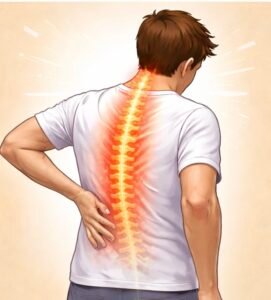

Back Pain

Back pain is one of the most common causes of disability.

It can occur due to disc problems, muscle strain, facet joint arthritis,

or nerve compression.Modern interventional pain treatments such as targeted injections,

radiofrequency procedures, and image-guided therapies can reduce pain

and improve mobility without major surgery.